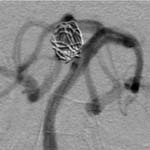

<³úµ¿¸Æ·ù>

<¼ö¼úÀü>

<¼ö¼úÈÄ>

ÀǽÄÀúÇϸ¦

ÁÖ¼Ò·Î ³»¿øÇÑ È¯ÀÚÀÇ Ç÷°üÃÔ¿µ¼Ò°ßÀ¸·Î

³ú±âÀúµ¿¸ÆÀÇ °Å´ë µ¿¸Æ·ù°¡ º¸À̰í ÀÖÀ¸¸ç±¹¼Ò¸¶ÃëÇÏ¿¡¼

³úÇ÷°ü³» ¼ö¼ú·Î µ¿¸Æ·ù³» ÄÚÀÏÀÌ »ðÀÔµÈ

¼Ò°ß